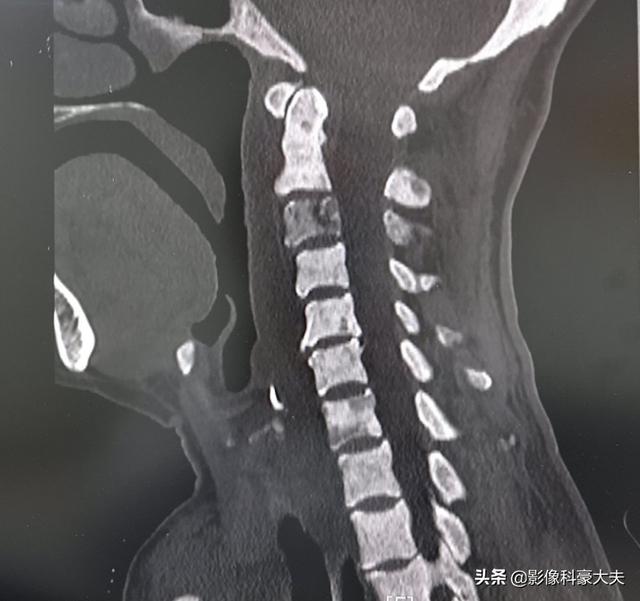

この老人は胃がんの患者で、手術前に首が少し痛いと言っていたが、その結果、頸椎CTで頸椎に広範な転移が見つかり、手術には適さなくなった。

- 手足の衰弱:頸椎に骨転移が生じると上肢に脱力感やしびれが生じ、腰椎に生じると下肢に脱力感が生じますが、このような手足の脱力感やしびれの症状は、通常、骨転移病巣が神経を圧迫することによって起こります。

骨転移は脊椎、特に腰椎に起こることが多く、骨転移の50%以上を占める。 肺がんや乳がんの患者の中には、最初の症状が腰痛で、次に大腿骨、骨盤と続き、肩甲骨や肋骨も問題になりやすい骨である。